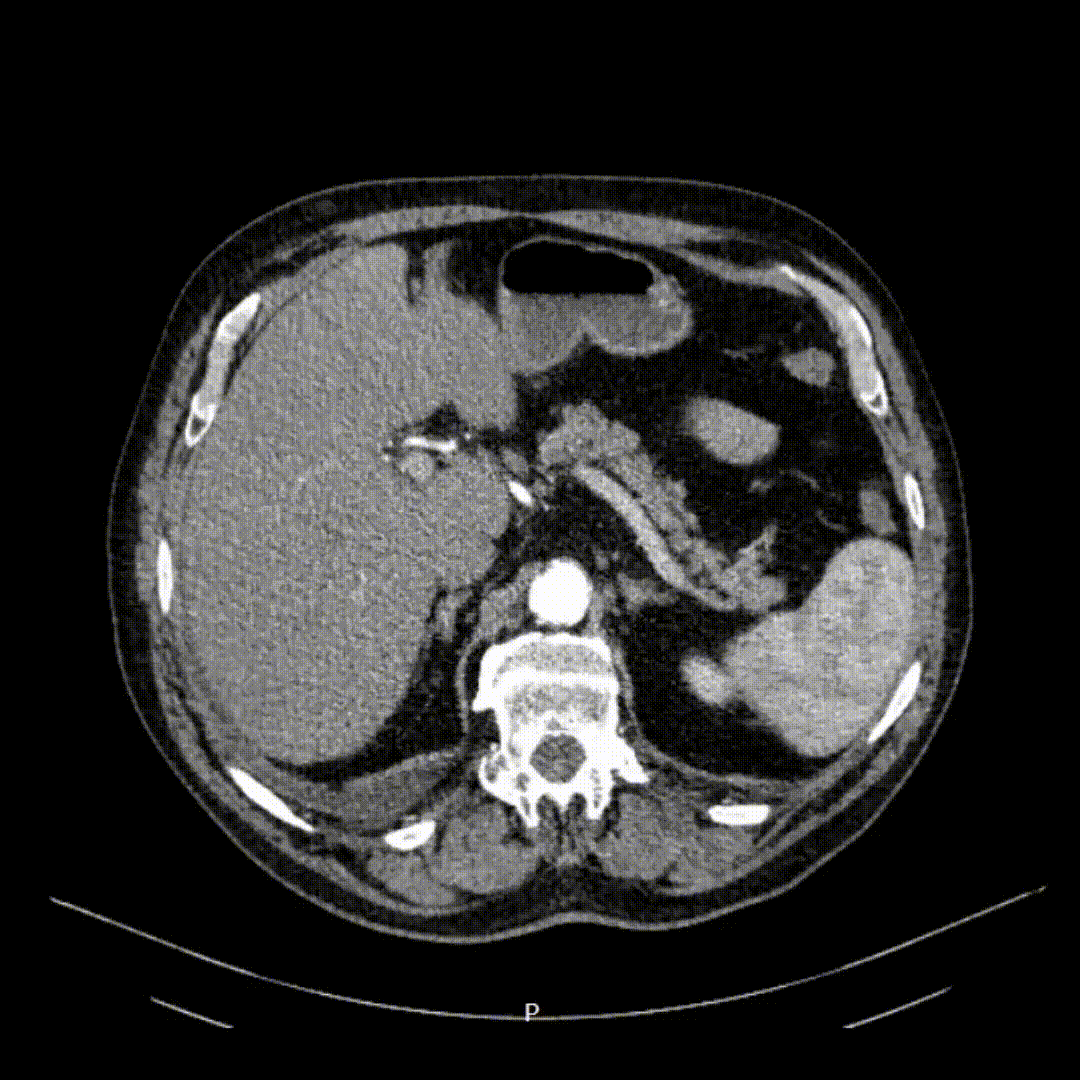

Известната компютърна томография до триизмерна реконструкция на вашата анатомия.

1. Пациентът предоставя изследването с КТ на екипа

2. Създаваме 3D модел на бъбрека, формацията, съдовете и други ключови структури

📌 Изисквания към КТ :

• Задължително с контраст

• Препоръчително разстояние между срезовете ≤ 1,5 mm (стандарт за външните КТ уреди)

• При 3 мм и повече разстояние между срезовете е възможно създаване на модел с по-ниско качество

⚖️ Качеството на изследването се преценява индивидуално от екипа на AssistoAR™.